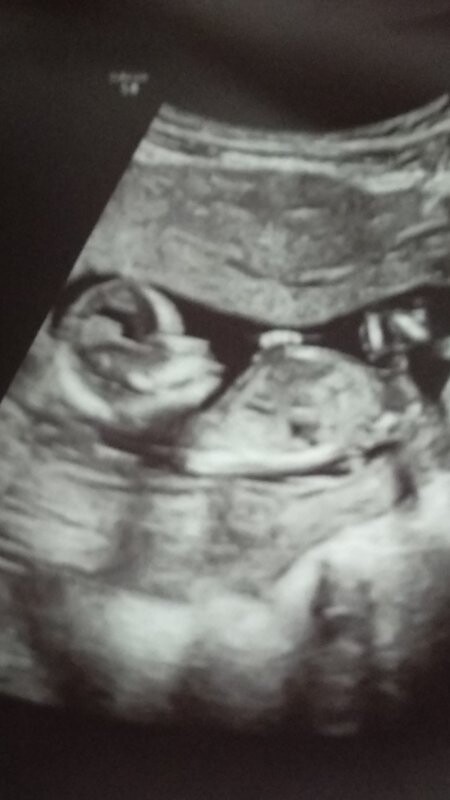

Dobrý denKolik dní to je podle velikosti reálné po ovulaci?Děkuji

Dobrý den,

jedná se o velmi časnou fázi těhotenství, přesně stáří Vám takto nelze říct, nicméně vzhledově embryo odpovídá cca 6.-7. gestačnímu týdnu.